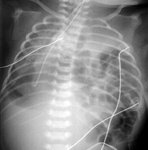

Fístula traqueoesofágica: sonda orogástrica torcida no esôfago

Do acervo de Ponthenkandath Sasidharan, MD; usado com permissão